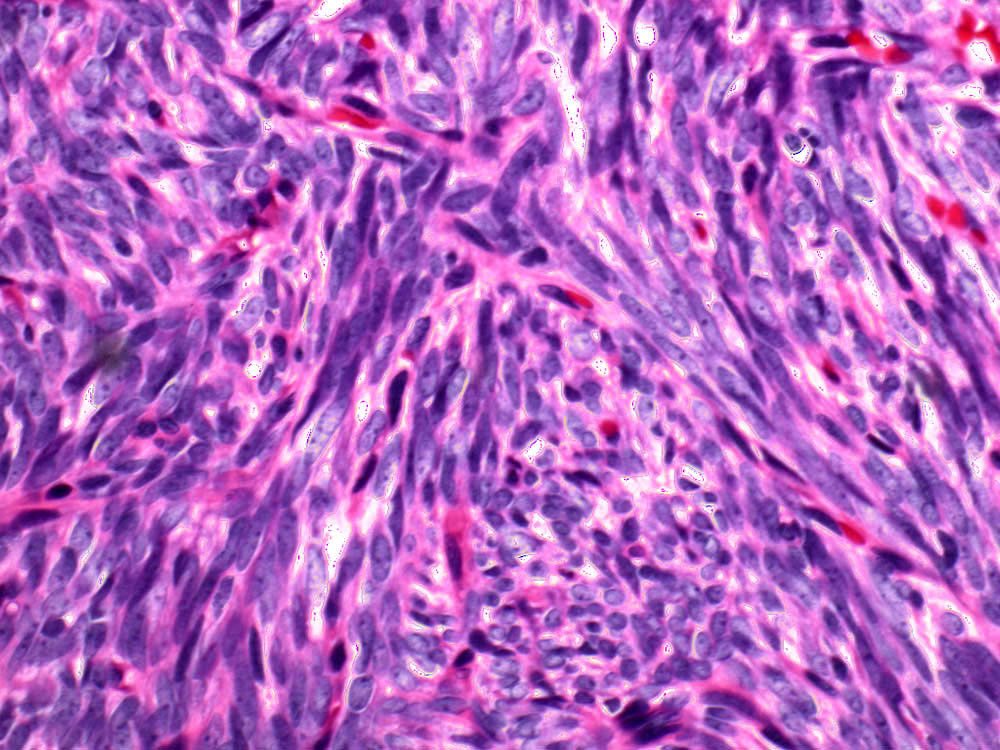

Case: ShoulderMass

Final Diagnosis: